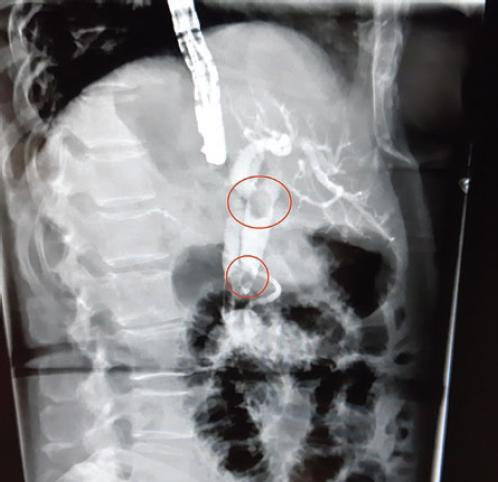

Como parte del protocolo diagnóstico se solicitan resonancia magnética (RM) y colangio-RM, que identifican un divertículo duodenal descrito como una cavidad de pared delgada, en la pared medial de la segunda porción del duodeno, además de coledocolitiasis y litiasis vesicular (Fig. 1). En la reconstrucción de la colangiografía se aprecia un divertículo de aproximadamente 3 cm que comprime la vía biliar, además de dilatación de la vía biliar de hasta 23 mm, con dos litos (uno en el tercio inferior del colédoco y otro por debajo de la carina) (Fig. 2).

Figura 3 Colangiopancreatografía retrógrada endoscópica que muestra la vía biliar intrahepática y extrahepática dilatada, con lito en la confluencia de los conductos hepáticos y en el tercio inferior.